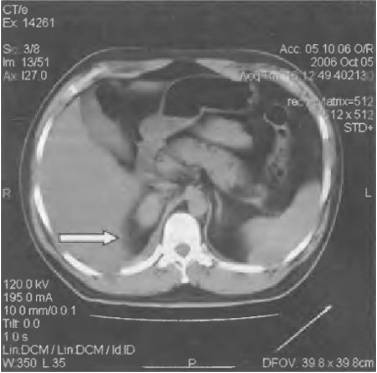

Забрюшинная гематома

Если болит правый бок и отдает в спину как лечитьОсложнение после травмы живота, которое также носит название забрюшинное кровоизлияние. Также гематома может развиться вследствие повреждения внутренних органов, таких как пищевод, органы мочеполовой системы, прямая кишка и пр.

Характер и локализация боли

Боль при патологии носит острый характер и усиливается при движении тазобедренных суставов.

Локализована боль, как правило, в животе, в боках сзади и в пояснице.

При незначительной гематоме пациент может не ощущать никаких признаков патологии. Симптоматика зависит от количества крови, излитой в брюшную полость, и от того, были ли повреждены внутренние органы и кости.

Значительная гематома сопровождается:

• сильным шоком;

• болевым шоком;

• внутренними кровотечениями;

• раздражением брюшины;

• парезом кишечника.

Диагностика и лечение

Определить наличие гематомы можно при помощи дифференциальной диагностики и УЗИ внутренних органов. Лечение хирургическое.